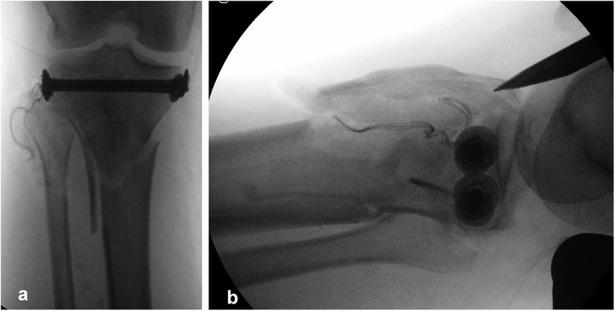

Bicondylar tibial plateau fractures have been treated with either plating or external fixation techniques, with conflicting results. A recently introduced technique involving the combined use of intramedullary nailing via a suprapatellar approach and condylar bolts could represent a new pathway toward better treatment of this severe injury.

The present report describes a retrospective and prospective study of all 17 patients (age range, 25 to 75 years) who were admitted under the author's care for the treatment of a closed, bicondylar tibial plateau fracture between 2013 and 2015. All patients consented to undergo fixation of the fracture with intramedullary nailing through a suprapatellar approach and with use of condylar bolts. The reconstructed articular surface was supported with freeze-dried allograft that had been previously soaked in concentrated bone marrow. The patients were followed at regular intervals, and the results were assessed with the Knee injury and Osteoarthritis Outcome Score (KOOS).

双髁胫骨平台骨折的治疗方法有钢板固定或外固定技术,但结果存在争议。最近引入的一种技术,即通过髌上入路联合使用髓内钉和髁螺栓,可能为更好地治疗这种严重损伤开辟一条新途径。

本报告描述了一项回顾性和前瞻性研究,研究对象为2013年至2015年间在作者治疗下因闭合性双髁胫骨平台骨折入院的所有17例患者(年龄范围25至75岁)。所有患者均同意采用髌上入路髓内钉固定并使用髁螺栓固定骨折。用预先浸泡在浓缩骨髓中的冻干同种异体骨支撑重建的关节面。定期对患者进行随访,并采用膝关节损伤和骨关节炎疗效评分(KOOS)评估结果。